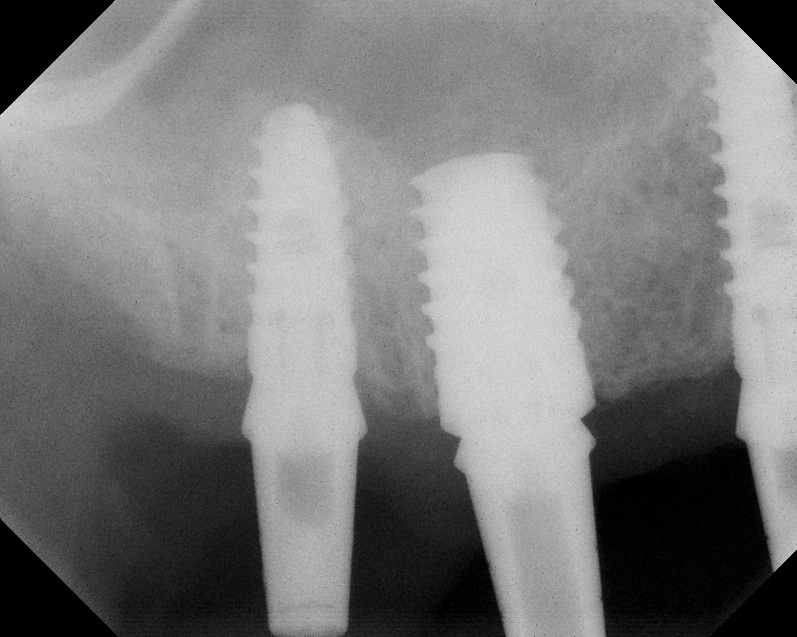

As with implant placement in general, use of a round bur is the first step in forming the osteotomy. As described above, to get verification of positioning—especially if a surgical stent is not used—a small piece of gutta percha can be placed inside this small osteotomy and a radiograph taken (Figure 1), after which the gutta percha is removed. The next step is the most critical, as it involves exposing the Schneiderian membrane. A 2-mm twist drill is used at a speed not exceeding 250 rpm, using a very light touch. Because the bone quality in the maxillary posterior is generally poor, it is usually easy to feel when the medullary bone has been breached and the dense cortical bone of the floor of the sinus has been reached. The cortical plate of the floor of the sinus should have been carefully measured with periapical radiographs presurgically, but it is usually about 1 mm in thickness. The most important and technique-sensitive part of this procedure is breaching the cortical plate of bone lining the sinus without tearing the sinus membrane. With a solid finger rest, good control, very light drilling pressure, copious irrigation, and a slow drilling speed, a slight “give” occurs once this plate of bone is breached. The full width of the twist drill should not penetrate the sinus floor; otherwise, the membrane will be torn. If it is not clear whether the membrane has been exposed, a flat-ended implant probe (Figure 2) can be used by inserting it into the osteotomy and feeling for the slight “give” or movement of the membrane. If the surgeon is not sure if the membrane is exposed, a radiographic marker can be used (Figure 3). If the membrane is significantly exposed, however, a radiographic marker should not be used, as this can inadvertently tear the membrane. The patient should also be warned not to bite down on the marker during the radiograph to avoid a membrane tear, and floss must be attached to the marker, so it can be retrieved if necessary.

Radiograph of gutta percha placed at the base of the initial osteotomy with a round bur to verify location.

Fig. 1